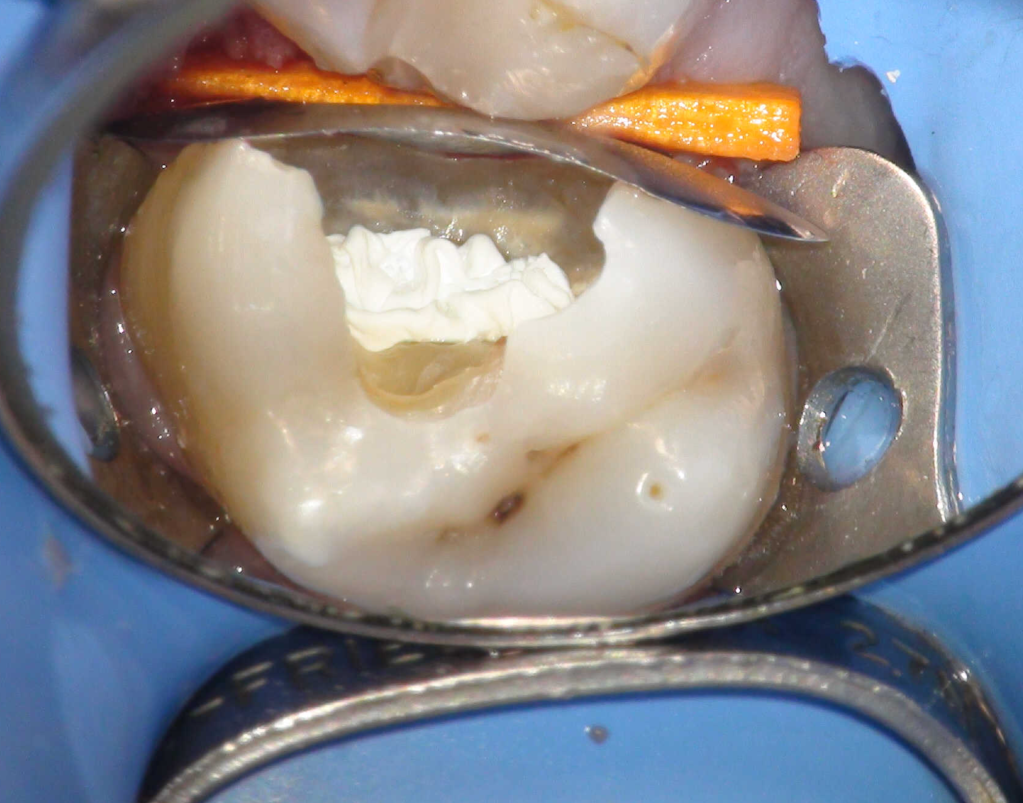

Pulpotomía biodentine + reco preendio